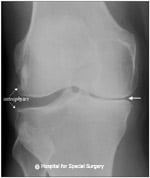

Regardless of the joint that is affected, conventional radiographs (X-rays) are used to evaluate your joint for osteoarthritis. The presence of osteoarthritis is displayed on the radiograph as a narrowing or a reduction in space between the bones of the joint where the cartilage has worn away, as well as by the formation of osteophytes (bone spurs) on the margins of the joint.

Anteroposterior (front to back) X-ray image of the knee showing osteoarthritis. Note the narrower spacing on the right side of the image, where cartilage has degenerated.

When cartilage is lost, bone rubs against bone. This can cause cysts or fluid-filled cavities in the bone, which will also be visible in an X-ray. The bone also responds with sclerosis (increased bone density), in which more bone grows under where the cartilage used to be. If the joint surfaces become misaligned, then osteophytes may form. There are basic routine X-ray views for imaging each joint:

Common findings of knee osteoarthritis from X-rays

Typically, the cartilage in one compartment of the joint (that is, the medial, lateral, or anterior patellofemoral joint compartment) is most severely affected. The standing X-rays may show narrowing of the involved joint space of the knee. Altered alignment of the knee joint is very common as either the cause or as a result of osteoarthritis. The patellofemoral joint (at the front of the knee) can be the focus of osteoarthritis of the knee or part of a more generalized condition. Lateral subluxation or patellar malalignment is very common.